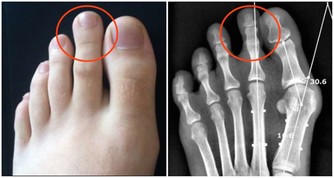

一、如果肝臟有了毒素表現在:

1.指甲表面有凸起的棱線,或是向下凹陷。中醫認為「肝主筋」,指甲是「筋」的一部分,所以毒素在肝臟蓄積時,指甲上會有明顯的信號。